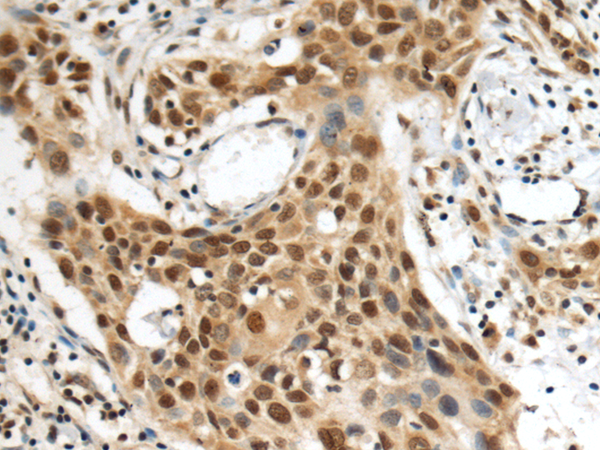

The image is immunohistochemistry of paraffin-embedded Human esophagus cancer tissue using P03523(POLB Antibody) at dilution 1/140. (Original magnification: ×200) |

The image is immunohistochemistry of paraffin-embedded Human gastric cancer tissue using P03523(POLB Antibody) at dilution 1/140. (Original magnification: ×200) |